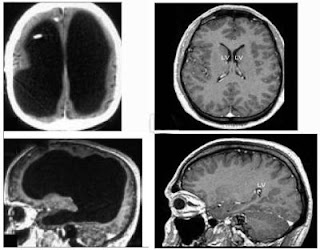

| Najmniejszy udokumentowany mózg (po lewej) Normalny mózg ludzki (po prawej) |

Fenomen ten odkryto przypadkowo, gdyż mężczyzna zgłosił się do szpitala z powodu, paradoksalnie, bólu nogi. Jego czaszkę prawie całkowicie wypełnia płyn mózgowo-rdzeniowy, który uniemożliwił mózgowi rozwój. Ale jak widać - nie miało to większego znaczenia. Na obrazku powyżej widać dwa mózgi. rzut z lewej przedstawia mózg francuza, czarne pole to płyn wypełniający czaszkę. Po lewej, dla porównania, widzimy normalny mózg. Różnica jest olbrzymia.